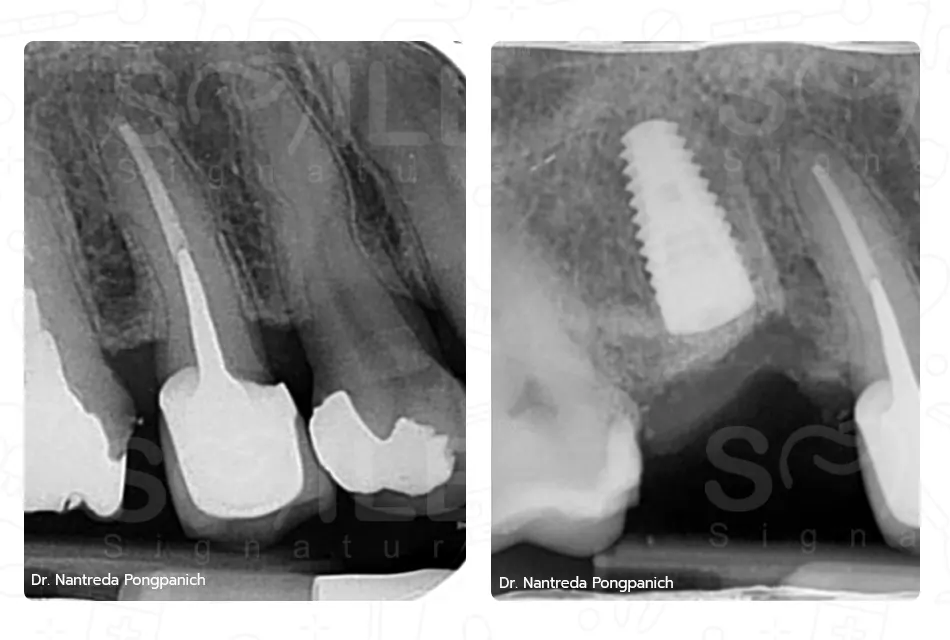

เฉพาะทางสาขาสาขาทันตกรรมรากเทียม, สาขาศัลยศาสตร์ช่องปาก และแม็กซิลโลเฟเชียล